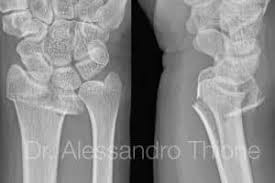

Sin embargo podría haber un daño a los nervios lo cual afectaría la funcionalidad. Cuánto tiempo debes evitar. Generalmente el rompimiento se encuentra aproximadamente una pulgada 25 centímetros por encima del lugar en el que el hueso se une a la muñeca.

Cuánto tiempo dura la rehabilitacion de. El extremo inferior del hueso se rompe bastante cerca del lugar donde se conecta con los huesos que pertenecen a la mano al lado del pulgar de la muñeca. Una quebradura de muñeca es una fractura o fisura en uno o más huesos de la muñeca.